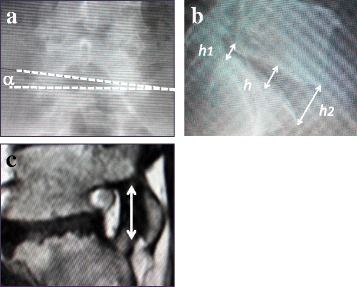

The pre- and postoperative wedging angle in the frontal view, lumbosacral height in the sagittal view in the standing lumbar X-ray image, and the bilateral foraminal ratio in the sagittal T1 WI in MR imaging were measured as radiographic parameters (Fig. 1). Instability at the final follow-up was also evaluated using plain X-ray.

Fig. 1.

Radiographic parameters. a L5-S1 wedging angle in a frontal standing plain X-ray. b Disc height of L5-S1 intervertebral disc: h = (h1 + h2) × 1/2. c Foraminal ratio: bilateral L5-S1 foraminal ratio of the narrower to the wider foraminal craniocaudal diameter